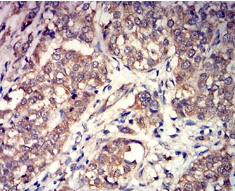

GRM3 Mouse Monoclonal antibody[6H132]

Immunogen :   Purified recombinant fragment of human GRM3 (AA: extra 433-576) expressed in E. Coli.

IHC    1/200 - 1/1000